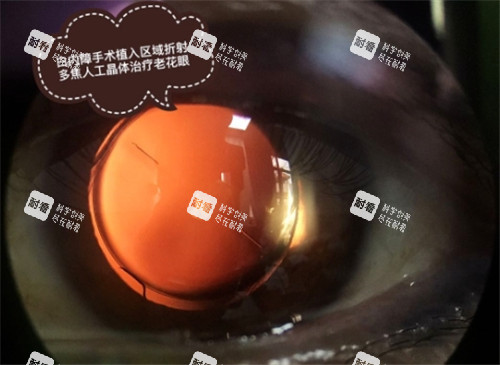

多焦点晶体:可同时满足远、中、近视力需求,减少对眼镜的依赖。

价格较高,约8000-15000元,适合追求生活便利性的中老年群体。